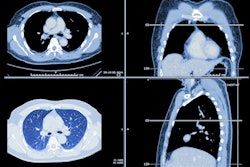

Dr. Melina Hosseiny of the University of California, San Diego, described an AI algorithm at ARRS 2023 designed as an aid for differentiating and diagnosing pneumonia and pulmonary edema. Image courtesy of Dr. Hosseiny.The researchers trained the multitask algorithm using two patient x-ray datasets, one from their university that included 26,798 images and one from RSNA that included 24,986 images. The datasets included a mixture of "less reliable" and "very reliable" images (as determined by expert radiologists) and were either labeled with the location of pneumonia or included NT-pro BNP lab measurements taken within 24 hours of the x-ray.